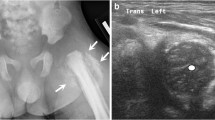

Other mechanisms of injury are less common. Newborns can sustain distal femoral physeal fractures from birth trauma, with identified risk factors including prolonged labor, macrosomia, and breech presentation [9]. Child abuse, sometimes identified through the presence of a subtle metaphyseal fragment or “corner fracture,” most commonly occurs in infants and toddlers [10]. As with all types of fractures, pathologic fractures can occur with lower energy mechanisms due to underlying metabolic bone disease or osteopenia, and nonambulatory patients with cerebral palsy and other neuromuscular disorders may sustain distal femoral physeal injuries from falls or direct blows .

The role of ultrasonography (US) is limited to physeal fractures in infants and newborns, but may help assess displacement of a distal femoral fracture in which there is minimal developmental ossification [23].